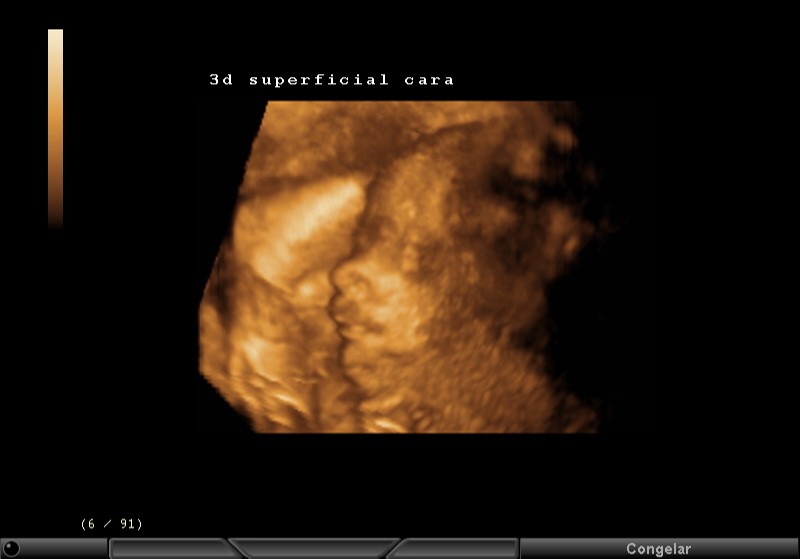

3D SUPERFICIAL, CARA, BOCA, NARIZ, PARPADOS

3D SUPERFICIAL PERFIL CARA